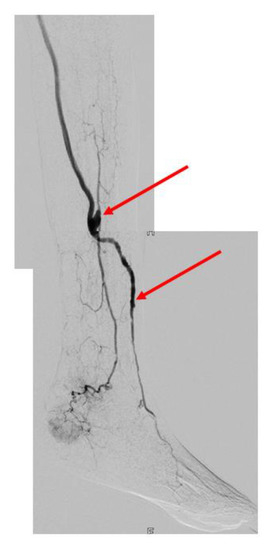

3.2. Bypass Configuration